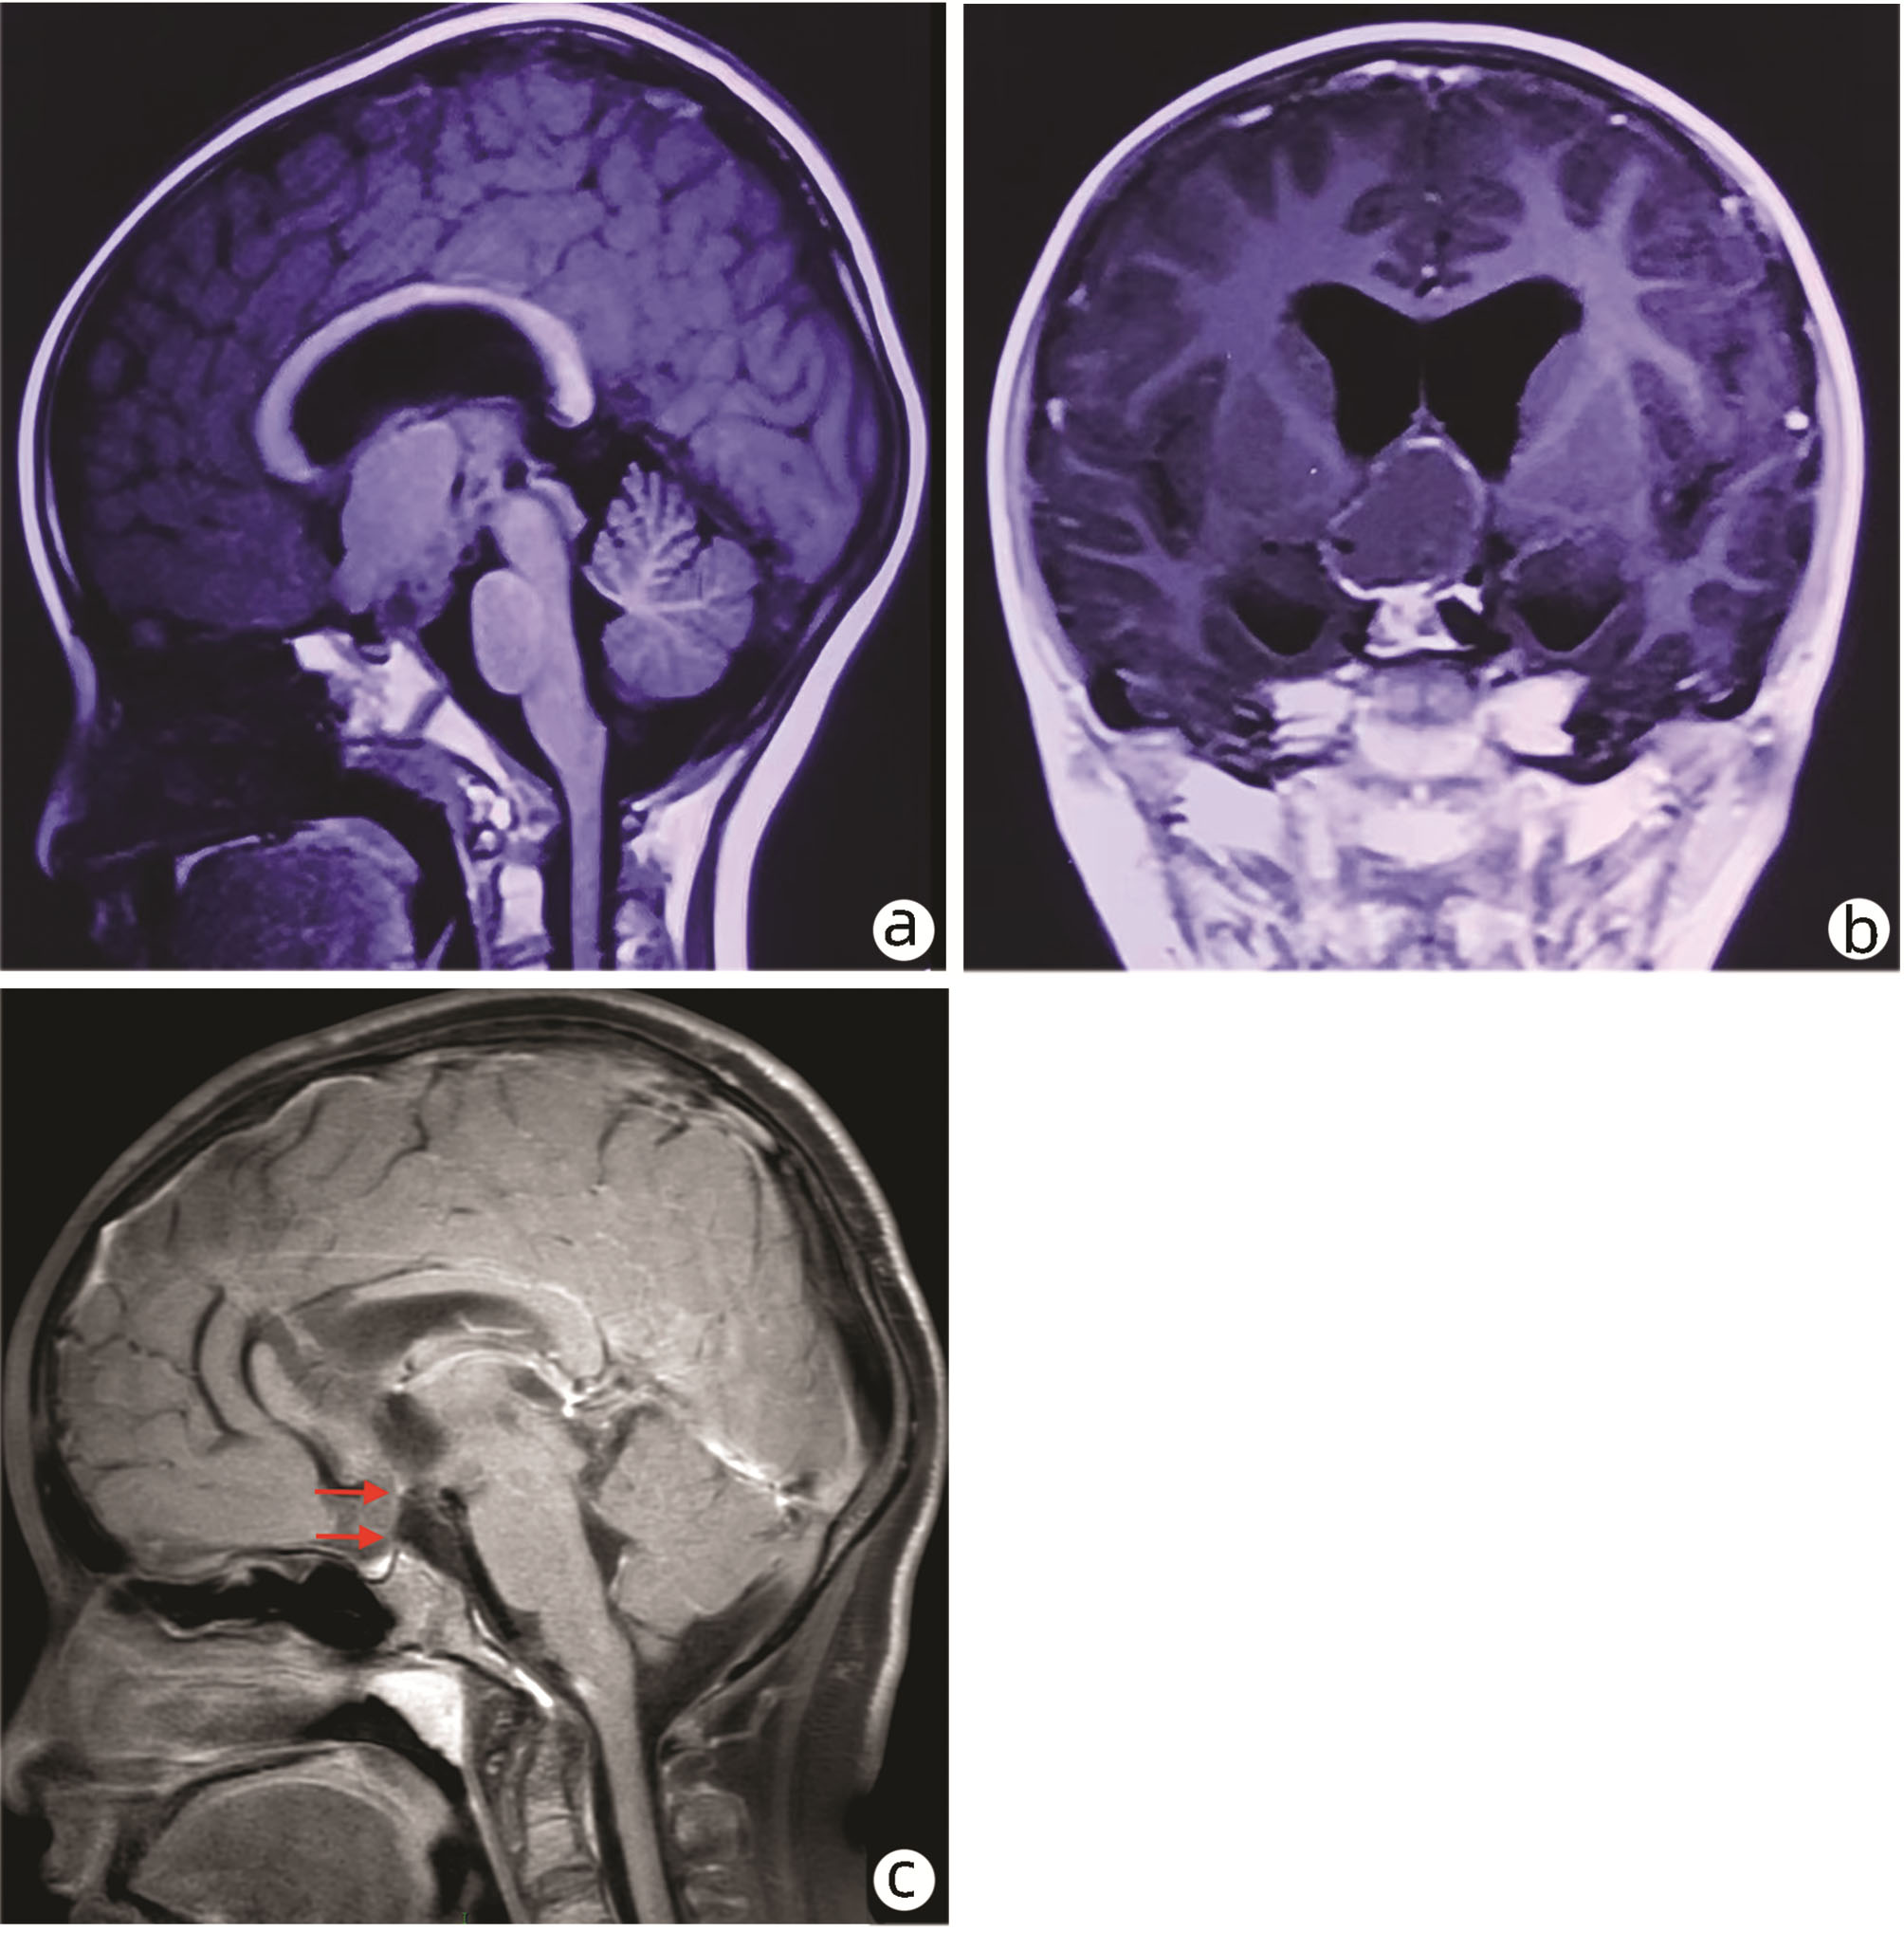

Whole genome analysis of a Wilson's disease family

Yaxin HU, Zhuo CHENG, Shuo CONG, Yongmei LIU, Baofang ZHANG, Yu LEI, Zhao YAN, Yiwei ZHANG, Xi PU, Lei YU, Mingliang CHENG

2022, 38(7): 1616-1619. DOI: 10.3969/j.issn.1001-5256.2022.07.029

Abstract(1099) HTML (347) PDF (3028KB)(101)

Abstract: